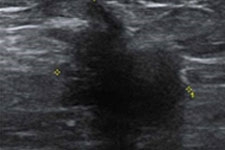

초음파검사에서 혹이 관찰되면, 이 혹이 내부가 액체로 되어 있는 물혹이나 고름주머니인지, 아니면 증식된 종양 세포들로 이루어진 덩어리, 즉 종양인지를 구분할 수 있습니다.

물혹은 검은 음영으로, 종양은 회색음영으로 나타납니다.

그리고 종양의 모양을 보고도 양성 종양인지, 악성 종양(암)인 지를 구별할 수 있습니다. 양성 종양은 가장자리가 매끈한 모양으로 많이 나타나지만, 악성 종양의 경우는 주위 조직으로 번져나가는 특징이 있기 때문에 가장자리가 삐죽삐죽 튀어나온 불규칙한 모양으로 나타나는 경우가 많습니다.

물혹(낭종) 양성종양 암